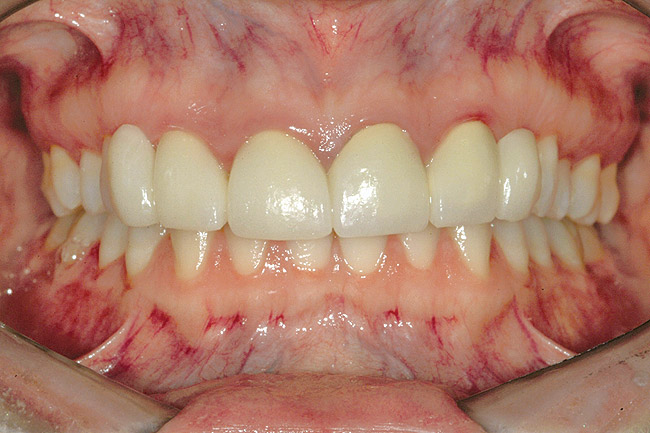

Fig 6 (and Fig 7). Prerestorative orthodontics was completed in 5 months. Final result 3 years, 4 months after completion.

Figure 6

Fig 7 (and Fig 6). Prerestorative orthodontics was completed in 5 months. Final result 3 years, 4 months after completion.

Figure 7

Fig 8 (and Fig 9). Teeth Nos. 5 and 12 were converted to Nos. 6 and 11, and Nos. 6 and 11 were converted to Nos. 7 and 10. Nos. 4 and 13 were enlarged. Note stability and absence of orthodontic relapse. Before-and-after smiles. Periodontist: Edward P. Allen, DDS, PhD. Prosthodontist: Robert R. Winter, DDS.

Fig 9 (and Fig 8). Teeth Nos. 5 and 12 were converted to Nos. 6 and 11, and Nos. 6 and 11 were converted to Nos. 7 and 10. Nos. 4 and 13 were enlarged. Note stability and absence of orthodontic relapse. Before-and-after smiles. Periodontist: Edward P. Allen, DDS, PhD. Prosthodontist: Robert R. Winter, DDS.